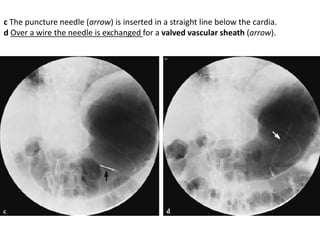

infiltration extending

into the duodenum,

although this was not

appreciated at

endoscopy

Staging of Gastric Carcinoma

• The TNM classification system